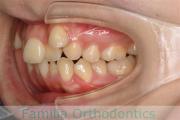

No.23V-061

- 主な症状:

- 叢生

- その他の症状:

- 上下顎前突

- 年齢:

- 23歳

- 性別:

- 女性

- 抜歯部位

- 上:

- 44

- 下:

- 主な使用装置:

- FEA 022

- 治療にかかった費用:

- 88万円

でこぼこを綺麗に並べたいということで来院されました。上下左右から小臼歯を抜歯して、マルチブラケット法を2年半、30回程度通院していただいて行いました。

かなり強い叢生(でこぼこ、凹凸、ガタガタ)のため、保定をしっかりしないと後戻りのリスクが高いケースといえます。

- ≫治療前

-